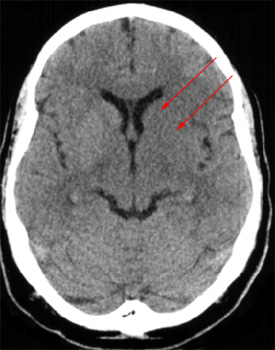

Head CT > Stroke > Lentiform Nucleus Obscuration

Lentiform Nucleus Obscuration

Lentiform nucleus obscuration is due to cytotoxic edema in the basal ganglia. This sign indicates proximal middle cerebral artery occlusion, which results in limited flow to lenticulostriate arteries. Lentiform nucleus obscuration can be seen as early as one hour post onset of stroke.